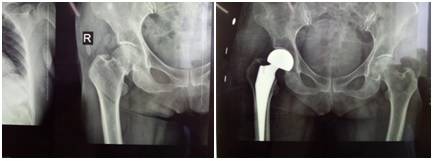

隨著救護(hù)車的呼叫,我科接收一名由西安某國(guó)內(nèi)知名三甲醫(yī)院轉(zhuǎn)來的85歲股骨頸骨折女性患者,患者因雙膝退行性骨關(guān)節(jié)病,導(dǎo)致膝關(guān)節(jié)嚴(yán)重屈曲內(nèi)翻畸形,活動(dòng)不便在家摔倒,確診為右側(cè)股骨頸骨折,擬行人工關(guān)節(jié)置換術(shù),完善術(shù)前檢查,心臟彩超示EF值41%,該醫(yī)院骨科、麻醉科會(huì)診后表示手術(shù)存在絕對(duì)禁忌癥,與患者家屬溝通后拒絕手術(shù),兒女們痛心疾首,撕心裂肺的哭泣,看不到任何希望,患者家屬抱著最后一絲希望,輾轉(zhuǎn)多家三級(jí)醫(yī)院就診,均以手術(shù)禁忌癥,拒絕收治。我科張富軍主任目前就讀于第四軍醫(yī)大學(xué),攻讀博士學(xué)位,了解到該名患者情況后,與患者家屬積極溝通、協(xié)調(diào)后,患者轉(zhuǎn)入我科治療,入院后,主管醫(yī)生張浩依據(jù)各項(xiàng)檢查及相關(guān)科室會(huì)診記錄,通過全科討論,制定治療方案,經(jīng)請(qǐng)心血管內(nèi)科會(huì)診,制定改善心功能治療措施,給予利尿、營(yíng)養(yǎng)心肌,減輕心臟負(fù)荷等相關(guān)治療措施,并在我科護(hù)理組精心護(hù)理下,積極預(yù)防臥床并發(fā)癥的發(fā)生,與患者及家屬多次溝通,強(qiáng)調(diào)手術(shù)風(fēng)險(xiǎn),同時(shí)給患者及家屬建立戰(zhàn)勝病魔的信心,經(jīng)治療1周后,全面復(fù)查各項(xiàng)術(shù)前檢查,心臟彩超檢查EF值57%,余各項(xiàng)檢查未見手術(shù)絕對(duì)禁忌癥,我科再次討論后決定行人工關(guān)節(jié)置換術(shù)。術(shù)前張富軍主任、麻醉科龐曉宏主任與患者家屬全面、詳細(xì)溝通麻醉、手術(shù)風(fēng)險(xiǎn),圍手術(shù)期并發(fā)癥及術(shù)后預(yù)期恢復(fù)情況,患者家屬?gòu)?qiáng)烈要求手術(shù),表示放手一搏,諒解手術(shù)意外,經(jīng)報(bào)請(qǐng)醫(yī)務(wù)科備案,于8月2日在硬腰聯(lián)合麻醉下對(duì)患者實(shí)施右側(cè)人工股骨頭置換術(shù),手術(shù)在緊張的氣氛下于上午9點(diǎn)開始,14分鐘后成功安裝假體,宣布手術(shù)結(jié)束,患者生命體征平穩(wěn),傷口采用美容縫合,于10點(diǎn)安返病房,次日在醫(yī)護(hù)人員協(xié)助下順利下床站立,經(jīng)全科醫(yī)護(hù)人員的悉心照料下,患者于8月10日懷著感恩的心順利出院,患者出院時(shí)的一句話,“你們是我的救命恩人”,感動(dòng)全科醫(yī)護(hù)人員。